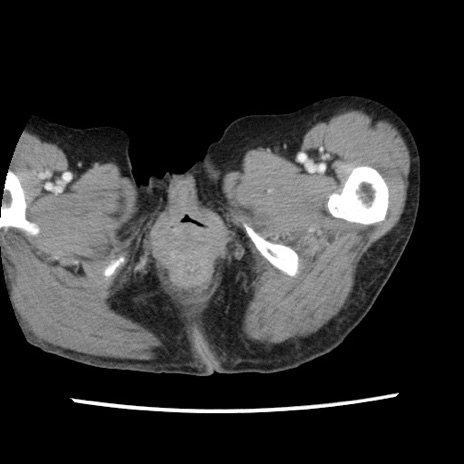

症例1(横断像)

【症例】80歳代女性

【主訴】腹痛

【現病歴】8時間前から腹痛あり来院。

【既往歴】糖尿病、脂質異常症、子宮体癌にて子宮全摘術

【身体所見】意識清明・会話良好だが腹痛で苦悶様、全腹部にわたって反跳痛と圧痛あり

【データ】WBC 13600、CRP 0.14、LDH 224、CK 90